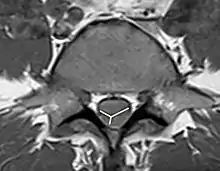

As the non-contrast CT and spine CT angiography are ineffective in imaging modalities, doctors use MRI to confirm the diagnosis. MRI findings, including pencillike hyperintensities on T2-weighted sagittal images and "owl's eyes" or "snake eyes" sign on T2 axial images, indicate the infarction is predominately in the watershed area of the gray matter of ventral horn (anterior spinal artery infarct).[10] Also, posterior paramedian triangular hyperintensity in T2 hyperintensity indicates posterior spinal artery infarct. On a T1 sequence, we may also observe a cord expansion and a decreased signal.[18] However, traditional MRI may show no abnormality especially for those patients in the acute phase.[8] DWI is very sensitive for early detection of spinal cord infarction and shows a typical high signal intensity.[19]